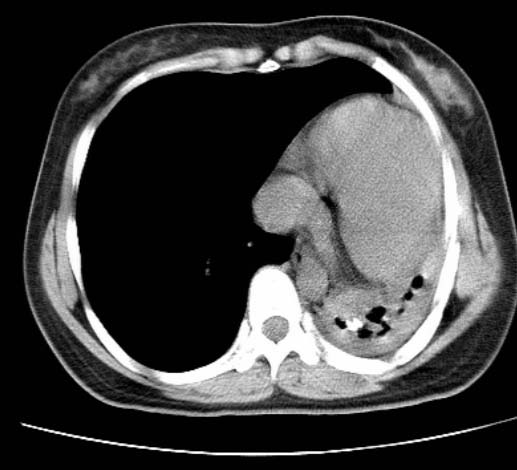

标题: CT25648:求教:是肺发育不全还是结核?

女  20岁。一月前咳血,诊“肺结核”抗痨治疗一月后,咳血停止,现复查。病人精神好。前后ct片对比未见明显变化。既往体检“正常”

1)考虑左肺结核并肺不张、支气管扩张。2)纵隔疝。

考虑左肺结核,左肺毁损,纵膈左偏,既往体检正常不可靠,tb一个月也不会这个样子的,有钙化,应该病程较长,冰冻三尺非一日之寒!

左肺发育不全。